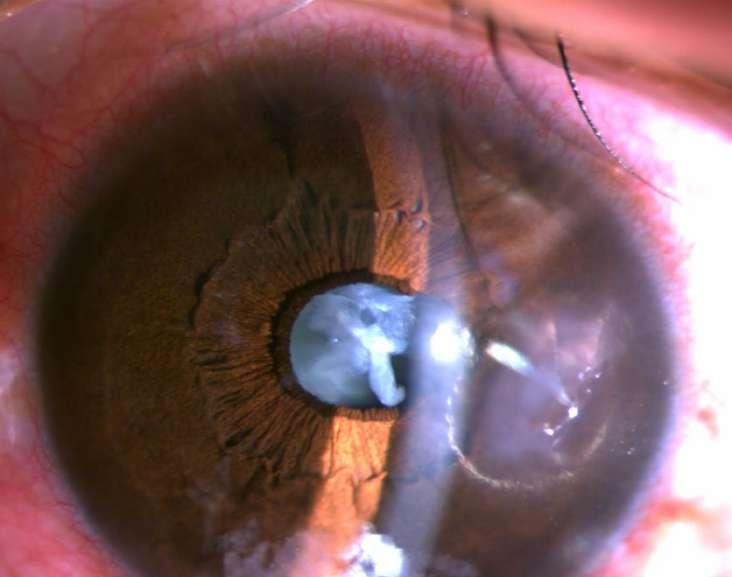

Imágenes aportadas por Dr. Nathan Dukes

ü Imagen A, B y C muestran Subluxación del lente intraocular en paciente con pseudoexfoliación. Sin antecedentes de trauma previo.

ü El síndrome de pseudoexfoliación es un desorden de la matriz extracelular, relacionado con la edad, caracterizado por la producción y depósito de un material brilar en varios tejidos intraoculares y extraoculares.

ü Puede ser unilateral o bilateral y es un factor de riesgo mayor para desarrollar glaucoma secundario de ángulo abierto.

ü Consotuye la causa idenocable más común de glaucoma en el mundo y la causa más frecuente de glaucoma unilateral.

10.B. SUBLUXACIÓN DE LENTE INTRAOCULAR EN PACIENTE CON SD. DE

PSEUDOEXFOLIACIÓN

B C Spinel JE, Alonso MP. Sindrome de pseudoexfoliación